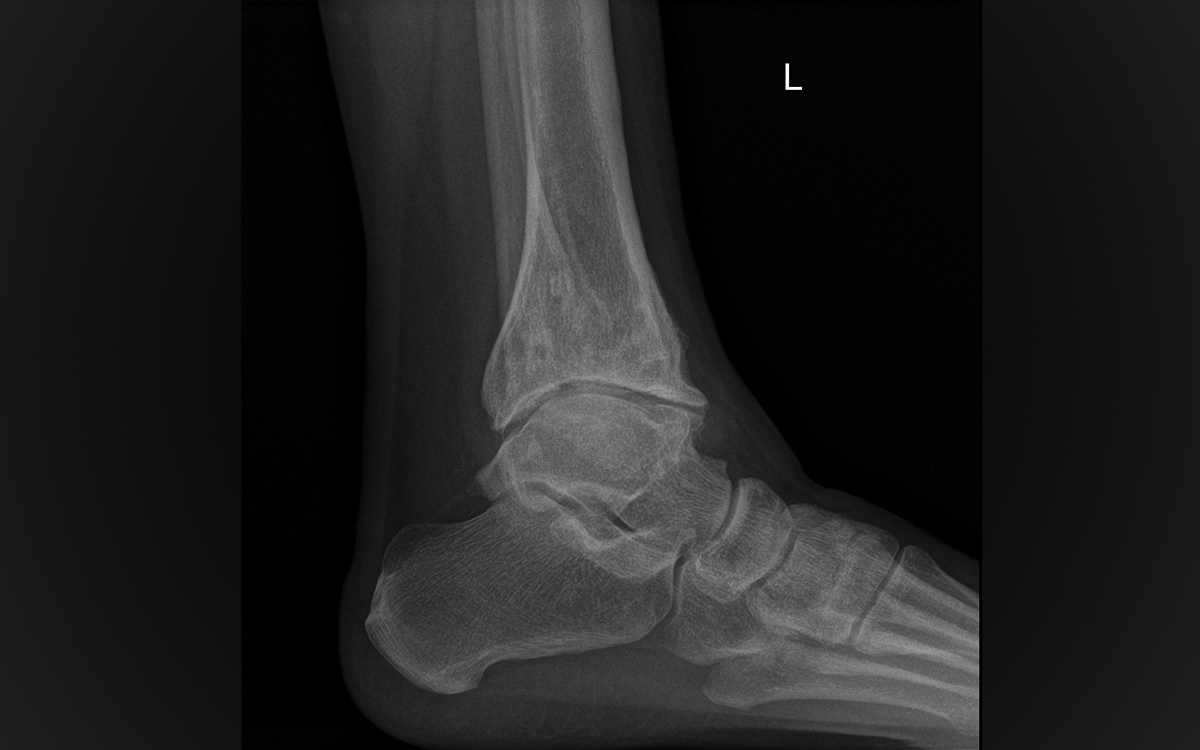

The ankle joint is a mortise joint, with the talar bone fitting into the tibia. It has a 1 mm tolerance for any irregularity. If the joint or the bones above and/or below are fractured or if the ligaments around the ankle are damaged, the joint can progress down a degenerative pathway to arthritis. Yet if it remains uninjured, people can walk and run on this small joint for a lifetime without ever developing the arthritis that plagues the hips, knees, and other joints.

Ankle joint replacement has a checkered history, with failures rampant amongst active patients. Over time, the designs have improved and the courage of surgeons to use them has increased. The problem remains that the bones of the tibia and the talar bone of the ankle, once diseased or injured, do not hold the components of the artificial joint well. The surfaces are just too small and the body weight upon them too large.